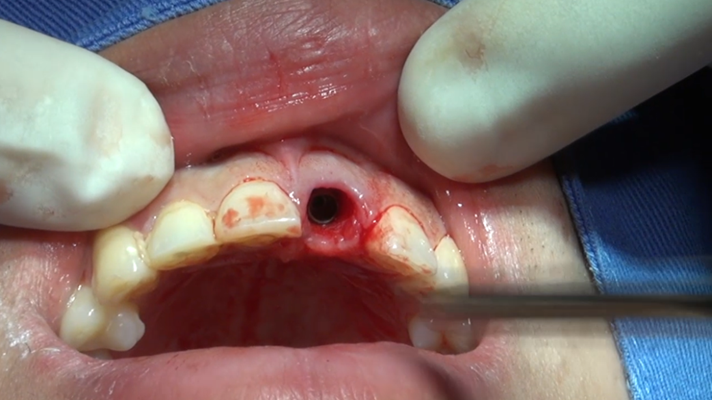

Clinical case: Extraction, immediate placement & loading using

R2GATE solution in aesthetic zone

- Courtesy of Dr. Jong-Cheol Kim, Korea-

Dr. Jong Cheol Kim, immediate loading, digital guided surgery, Digital ONE-DAY Implant, maxillary anterior, #21, guided surgery, immediate loading, AnyRidge, R2GATE, Mega ISQ, MEG Torq, R2GATE Full Surgical Kit

AnyRidge implant system, R2 Guide, R2GATE Full Surgical Kit, Mega ISQ